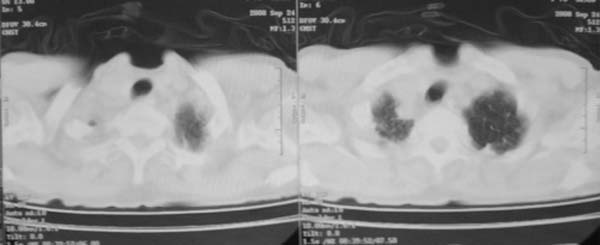

颈部见多枚淋巴结肿大,考虑尘肺继发结核,喉部淋巴结钙化,不除外喉部慢性淋巴结炎、喉淀粉样变及类癌等

颈部多个肿大淋巴结,考虑矽肺并结核

符合矽肺,另外甲状腺可见病变,需强化明确.

考虑尘肺继发结核,喉部淋巴结钙化,不除外喉部慢性淋巴结炎。

双上肺结节融合影,周围有纤维条索影,结合粉尘接触史,首先考虑尘肺。双侧颈部有增大淋巴结,有声嘶表现,肺癌淋巴结转移不能排除。可结合颈部淋巴结活检。